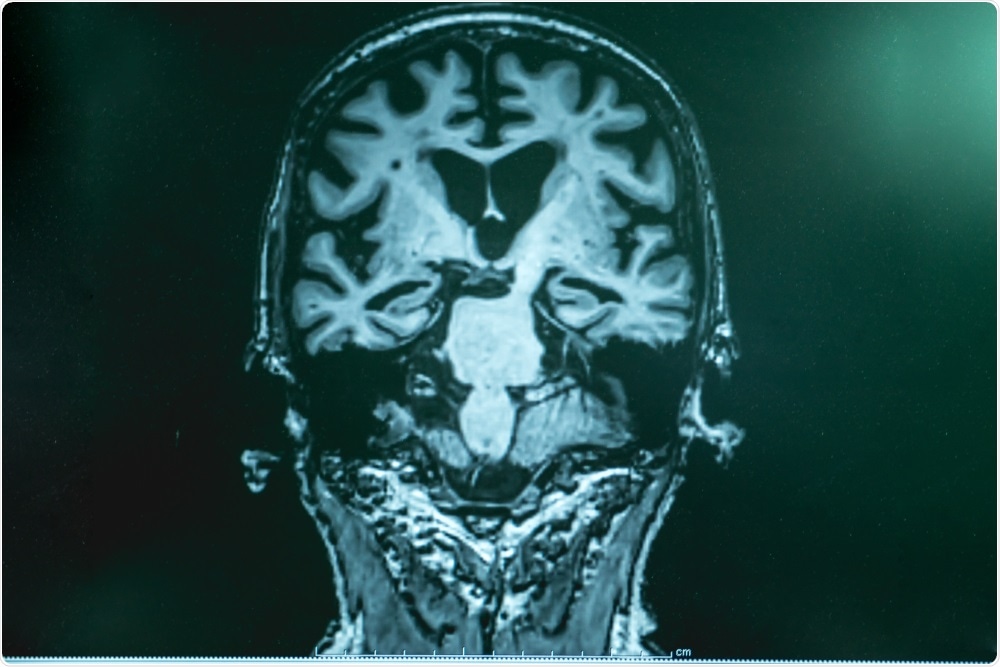

Image Credit: Gorodenkoff/Shutterstock.com

Furthermore, within the last couple of decades, advances in computer technology have led to the emergence of computational neuroscience, and advances in imaging techniques have greatly improved diagnostic and research imaging tools to study brain structure and function.

Cognitive and behavioral neuroscience focuses on how psychological functions are produced in the brain or related to neural activity. This can be studied using animal models or human subjects by an array of imaging techniques such as fMRI, PET & EEG, correlating brain signals (BOLD or electrical) to specific tasks or functions in the field of neuropsychology.